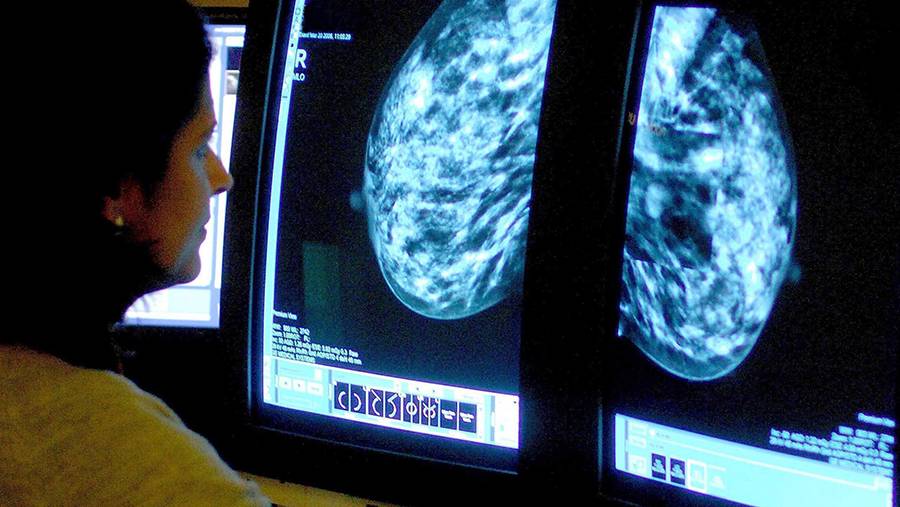

Онколог Серяков рассказал о признаках повышенного риска рака молочной железы

Фото: ТАСС/Rui Vieira

Рак молочной железы (РМЖ) — самый распространенный вид рака среди женщин, его часто выявляют уже на поздних стадиях, когда вылечить заболевание гораздо сложнее. Однако существуют факторы, которые указывают на то, что у женщины имеется повышенный риск онкологии молочной железы. О том, какие это признаки и как самостоятельно провести осмотр груди, в пятницу, 15 октября, «Известиям» рассказал главный онколог «СМ-Клиника», врач высшей категории, доктор медицинских наук, профессор Александр Серяков.

Для того чтобы выявить заболевание на ранней стадии, рекомендуется проходить самостоятельный осмотр груди с 20 лет каждый месяц, а также выполнять скрининг в возрасте 40–75 лет один раз в два года. При этом тем людям, которые входят в группу риска, это необходимо делать чаще. Для скрининга РМЖ проводится УЗИ или маммография. Причем проводить скрининг рекомендуется с пятого по 12-й день менструального цикла, если он есть.